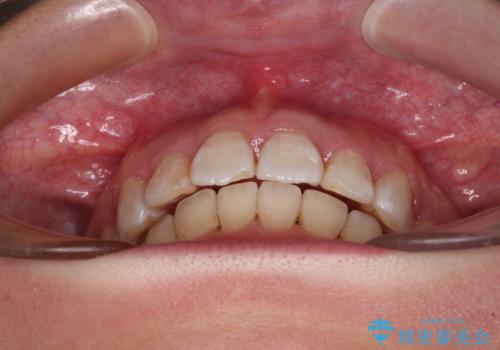

飛び出した前歯を引っ込めたい 目立たないワイヤーでの抜歯矯正

- 口元の閉じにくさと、前歯のでこぼこの歯並びを気にして来院された患者様です。

口元を積極的に引っ込めるために、上下左右の小臼歯計4本を抜歯することとしました。

咬み合わせが深く、咬合力強いため、補助装置を使用しながら積極的に口元を下げることとしました。